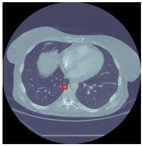

Table 12 demonstrates the results obtained from AlexNet with the SGD optimizer on the Luna16 dataset. The original image was benign, and the CNN architecture AlexNet with the SGD optimizer detected the image as benign. Next, the image was benign and AlexNet with the SGD detected the image as malignant, which was wrongly predict by AlexNet. The next image was malignant, and AlexNet with the SGD optimizer detected it as benign. Finally, the actual image was malignant, and AlexNet with the SGD optimizer detected it as malignant.

Table 12.

Detection results of AlexNet with the SGD optimizer on the LUNA16 dataset.